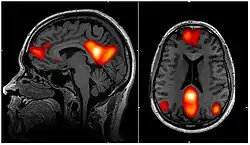

Dynamic functional connectivity (DFC) refers to the observed phenomenon that functional connectivity changes over a short time. Dynamic functional connectivity is a recent expansion on traditional functional connectivity analysis which typically assumes that functional networks are static in time. DFC is related to a variety of different neurological disorders, and has been suggested to be a more accurate representation of functional brain networks. The primary tool for analyzing DFC is fMRI, but DFC has also been observed with several other mediums. DFC is a recent development within the field of functional neuroimaging whose discovery was motivated by the observation of temporal variability in the rising field of steady state connectivity research.

fMRI is the primary means of investigating DFC. This presents unique challenges because fMRI has fairly low temporal resolution, typically 0.5 Hz, and is only an indirect measure of neural activity. The indirect nature of fMRI analysis suggests that validation is needed to show that findings from fMRI are actually relevant and reflective of neural activity.